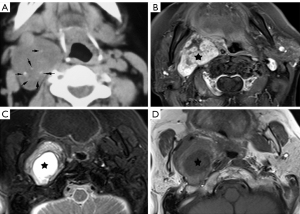

Schwannomas are benign tumors arising from Schwann cells surrounding peripheral nerves. Schwannomas in the carotid space most commonly stem from the vagus nerve. The tumor is usually a sharply demarcated round or oval mass with hypo-, iso-, or hyper-attenuation. Cystic degeneration, xanthomatous change, or areas of relative hypocellularity adjacent to densely cellular or collagenous regions usually contribute to heterogeneity of the tumor (Figure 1) (9,10). Schwannomas are hypovascular tumors, but in dynamic scans, they can show marked enhancement due to pooling of contrast agent resulting from poor venous drainage (11). More often, schwannomas demonstrate a variable degree of enhancement, most commonly patchy enhancement (Figures 2-7).

Due to its location between the vein and artery in the carotid space, schwannomas of the vagus nerve tend to separate the artery and vein, usually displacing the CCA/ICA medially and the IJV laterally (Figures 2,3) (12). Some schwannomas of the vagus nerve may displace the IJV and ICA/CCA in a posterior direction without splaying them and there is usually separation between the artery and vein (Figure 4). The cervical sympathetic chain runs in a fascial reflection posterior and slightly medial to the carotid space. Hence, schwannomas of the sympathetic chain tend to displace the IJV and CCA/ICA together, usually anteriorly and laterally (Figure 5) (5). A large schwannoma of the sympathetic chain may distort the surrounding anatomy and result in a posterior displacement of the carotid vessels without separation of the artery and vein (Figure 6) (13,14). Occasionally, a schwannoma of the cervical sympathetic chain may splay the internal and external carotid arteries at the carotid bifurcation but without encasing the arteries (Figure 7) (5). In these regards, the position of the tumor relating to the vessels in the carotid space is more important than the direction of vascular displacement. There has also been a reported case of schwannoma arising from the glossopharyngeal nerve in the carotid space causing posterior displacement of the ICA (15).